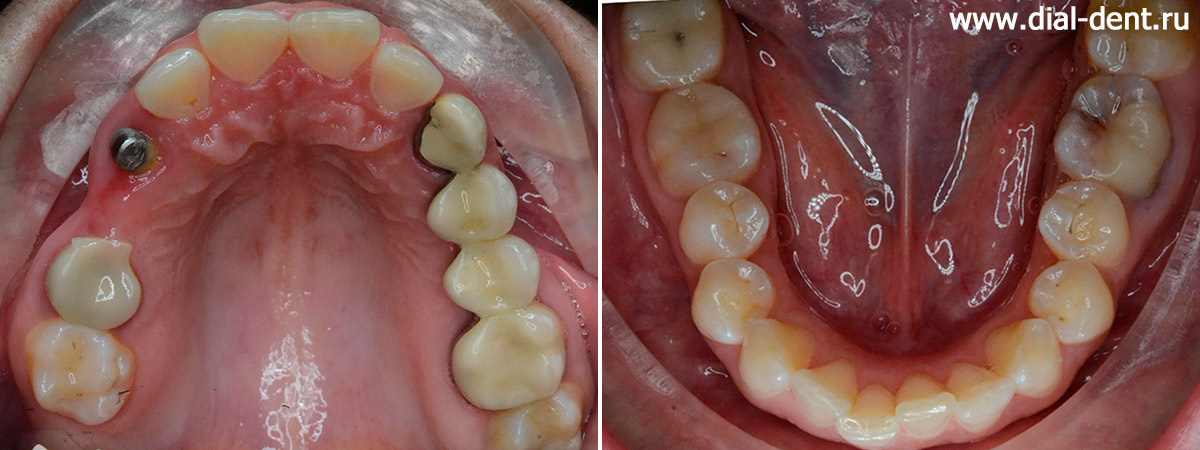

верхние зубы до и после комплексного лечения

нижние зубы до и после комплексного лечения